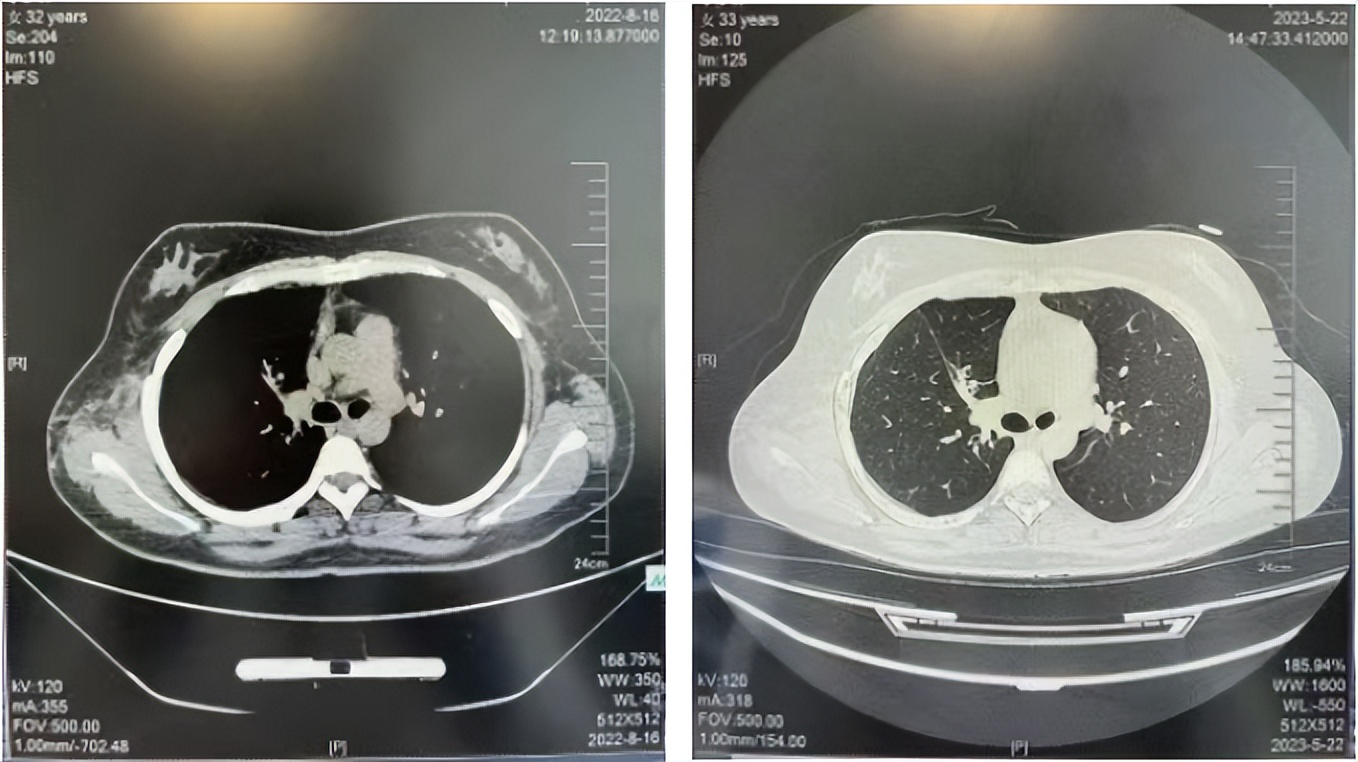

56岁,女性,无吸烟史饮酒史,既往体健。2023年02月患者体检发现肺占位性病变,胸部增强CT:右肺下叶后基底段结节;右侧锁骨上及纵隔内多发淋巴结肿大。PET-CT:右肺下叶周围型肺癌可能性大;1R、2L、3P、4R、4L及7组淋巴结转移可能性大。2023年02月就诊于本院胸外科行超声胃镜下纵隔肿物穿刺活检术,病理:结合免疫组化,符合肺腺癌。行NGS基因检测:EML4:exon20-ALK:exon20融合。PD-L1(克隆号22C3)TPS=55%。

2023年2月20日基线检查

2024年6月复查PR(最佳疗效)

2024年12月复查维持PR

2025年3月复查维持PR